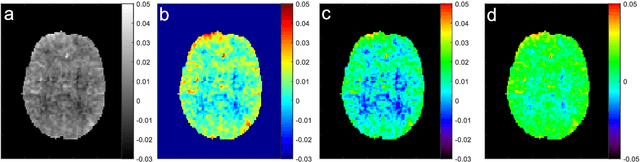

Abstract:Biophysical model fitting plays a key role in obtaining quantitative parameters from physiological signals and images. However, the model complexity for molecular magnetic resonance imaging (MRI) often translates into excessive computation time, which makes clinical use impractical. Here, we present a generic computational approach for solving the parameter extraction inverse problem posed by ordinary differential equation (ODE) modeling coupled with experimental measurement of the system dynamics. This is achieved by formulating a numerical ODE solver to function as a step-wise analytical one, thereby making it compatible with automatic differentiation-based optimization. This enables efficient gradient-based model fitting, and provides a new approach to parameter quantification based on self-supervised learning from a single data observation. The neural-network-based train-by-fit pipeline was used to quantify semisolid magnetization transfer (MT) and chemical exchange saturation transfer (CEST) amide proton exchange parameters in the human brain, in an in-vivo molecular MRI study (n=4). The entire pipeline of the first whole brain quantification was completed in 18.3$\pm$8.3 minutes, which is an order-of-magnitude faster than comparable alternatives. Reusing the single-subject-trained network for inference in new subjects took 1.0$\pm$0.2 s, to provide results in agreement with literature values and scan-specific fit results (Pearson's r>0.98, p<0.0001).